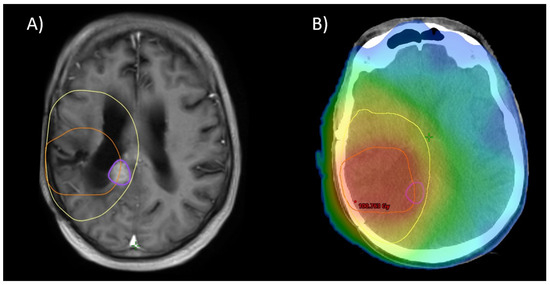

Figure 6. As depicted in Figure 1, 12 months after re-RT: (A) Further progression (purple) adjacent to the initial treatment site. Notice the site of progression was covered by the initial PTV (yellow) and partially covered by the re-RT PTV (orange). (B) shows a color wash dose distribution of a plan sum of initial RT and re-RT.

For 57 patients, the MRIs of further recurrence were all available in digital form. The patterns of relapse in these patients are described in Table 4, and a visual example is given in Figure 6. This analysis reveals no difference between the subgroups with in-field and marginal recurrence as the majority of cases (28 in-field recurrences, 26 marginal, 3 out-field). However, analysis of the initial patterns of relapse (leading to re-RT) reveals a tendency towards more out-of-field recurrence for patients treated with CeTeG (30% out-field vs. 14% for patients treated with TMZ, p = 0.11).